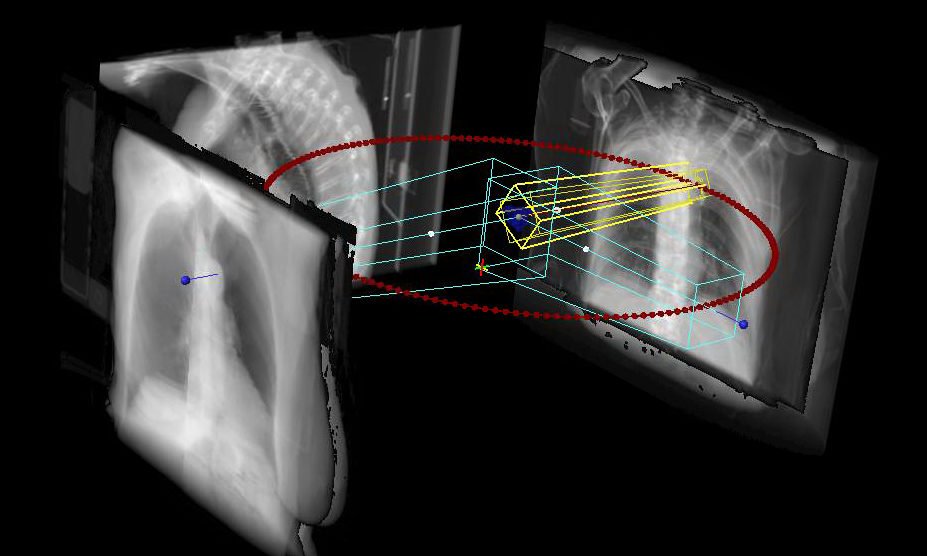

CT simulation has become an integral part of the treatment planning process. Ensuring that all systems involved in the simulation, planning, and then treatment process are accurately functioning is imperative.

OMPC can enhance your existing QA program by offering a complete end to end analysis of your simulation, planning and treatment process using the Lucy® 3D QA phantom. Using this single phantom, the following items can be evaluated:

CT Simulation laser accuracy

Spatial resolution

Image registration accuracy

Volume calculation accuracy

Tissue heterogeneity correction constancy (using CIRS phantom)

Dose calculation accuracy

In addition, CTDI and other diagnostic testing can be performed.